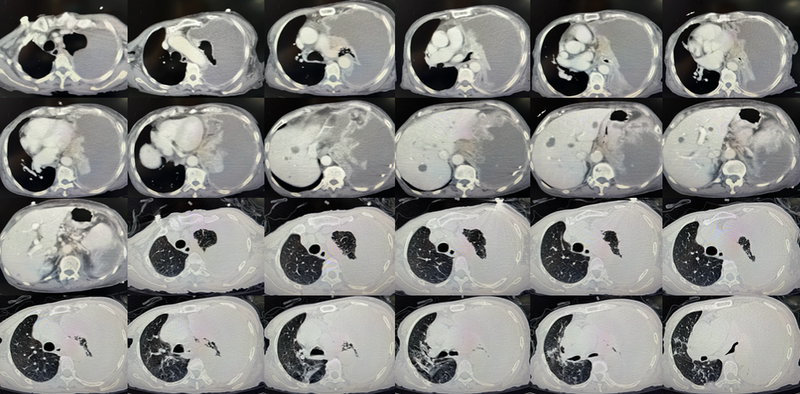

胸部CT如下图:

从上图CT可以看到,患者左侧大量胸水,即使引流了2L,似乎胸水并没有丝毫减少,左肺压缩只剩下很小一部分,纵隔也有向右侧推移的表现。仔细看还可以发现左侧胸膜有增厚。